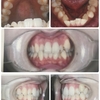

抜けた後の見た目はこんな感じです。

写真でいうと、左側です。

正面で軽く笑うくらいだったらそんなに目立たないかな?

ちょっと口を大きく開けると暗闇がw

横から見るとこんな感じ。

口が小さいので笑ってもそこまで見えませんが、器具つけるまでは謎の歯抜け女なのでちょっと気になるかな。